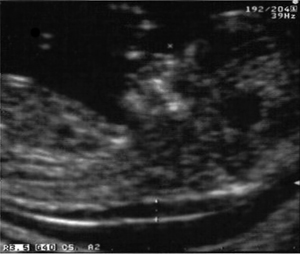

H αυχενική διαφάνεια αποτελεί την υπερηχογραφική εικόνα της συλλογής υγρού που φυσιολογικά εντοπίζεται πίσω από το ανώτερο τμήμα της σπονδυλικής στήλης του εμβρύου, μεταξύ της περιτονίας που καλύπτει την οπίσθια επιφάνεια της σπονδυλικής στήλης και του δέρματος (εικόνα 1).

Εικόνα 1. Αυχενική διαφάνεια και ρινικό οστό. Εικόνα 2. Υπερηχογραφικό screening πρώτου τριμήνου σε 2 στάδια.

Τα τελευταία χρόνια γνωρίζουμε ότι το ρινικό οστό (εικόνα 1) δεν απεικονίζεται στο υπερηχογράφημα των 11-14 εβδομάδων στο 70% των εμβρύων με σύνδρομο Down, στο 32% των εμβρύων με άλλες χρωμοσωμικές ανωμαλίες, καθώς και σε ένα ποσοστό φυσιολογικών εμβρύων, το οποίο, ανάλογα με την εθνικότητα, κυμαίνεται από 2-9%(42). Aν και σύμφωνα με την πρόσφατη μελέτη FASTER το ρινικό οστό ήταν παρόν σε τουλάχιστον 82% των περιπτώσεων με σύνδρομο Down,(43) τα περισσότερα δεδομένα συντείνουν στο ότι η απουσία του είναι πολύ συχνότερη σε έμβρυα με σύνδρομο Down(44-46) και μπορεί να αυξάνει τον κίνδυνο για το σύνδρομο κατά περίπου 30 φορές.(42)